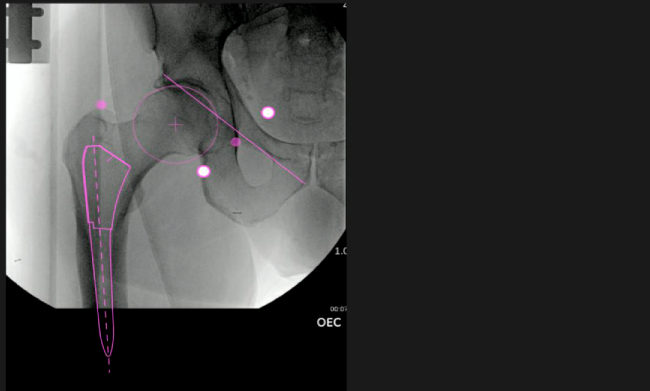

Planeación preoperatoria mediante la creación de plantillas digitales para reemplazo de cadera y análisis intraoperatorio

Favorece la restauración biomecánica del offset femoral.

Desplazamiento y offset para posicionamiento óptimo del componente (vástago) femoral.